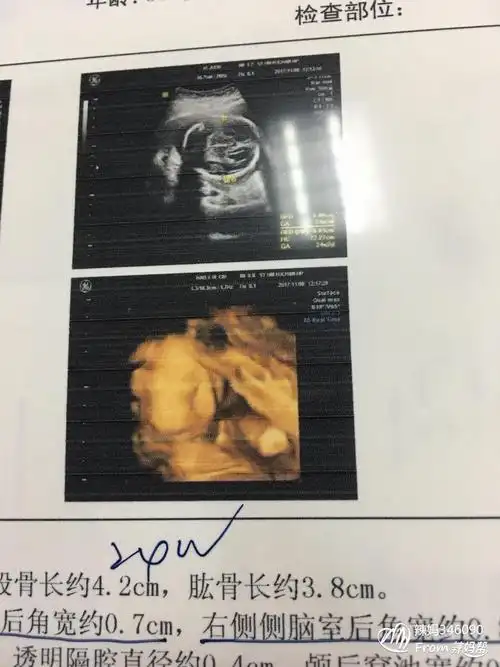

照四维的时候拍的,有没有会看男孩女孩的?第一胎,超好奇

怀七个月做的四维,哈哈,宝妈们看看这是男孩女孩

宝妈们来看看我的四维~是男宝女宝